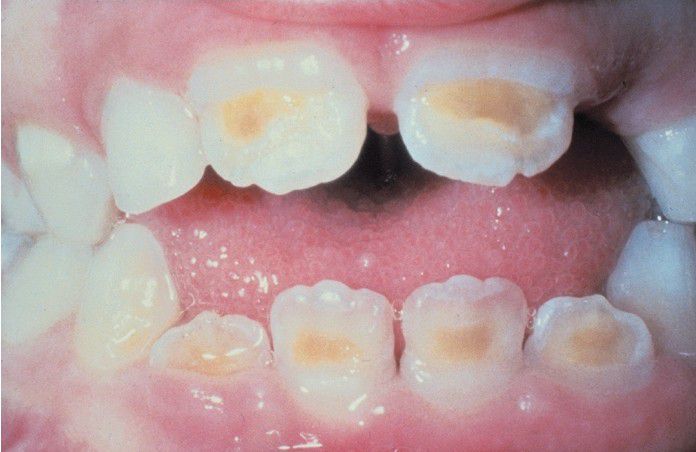

Enamel hypoplasia has affected the dentition of this patient, who had hypoparathyroidism while the teeth were forming.